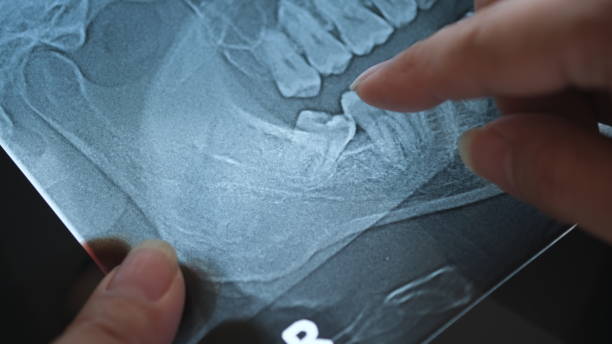

ضرس العقل هو أحد الأضراس الدائمة التي تظهر في مؤخرة الفم، وغالبًا ما ينمو بين عمر 17 و25 عامًا.

ورغم أن بعض الأشخاص قد لا يواجهون أي مشاكل عند ظهور ضرس العقل، فإن كثيرين يعانون من صعوبة في نموه بالشكل الصحيح، إما بسبب ضيق المساحة في الفك أو نموه بزاوية غير طبيعية. هذا الوضع قد يسبب مضاعفات إذا لم يتم التعامل معه في الوقت المناسب.

في سينتر دنت، نرى أن إهمال خلع ضرس العقل عند الضرورة قد يؤدي إلى مجموعة من المشكلات، منها:

• تزاحم الأسنان وتغيّر شكل الابتسامة: عندما لا يجد ضرس العقل مساحة كافية، يبدأ بالضغط على الأسنان المجاورة، مما قد يسبب تحركها من مكانها، وهو ما قد يتطلب لاحقًا علاجًا تقويميًا لإعادة ترتيب الأسنان.

• التهابات وتورم اللثة: في حالة نمو الضرس جزئيًا، تبقى أجزاء منه مغطاة باللثة، ما يخلق بيئة مثالية لتراكم البكتيريا وحدوث التهابات مزمنة مؤلمة.

• تسوس الأسنان المجاورة: صعوبة الوصول لتنظيف المنطقة حول ضرس العقل تسمح بتجمع بقايا الطعام والبلاك، ما يزيد احتمالية إصابة الضرس أو الأسنان المجاورة بالتسوس.

• تكوّن أكياس أو أورام حميدة: في حالات معينة، قد يتسبب الضرس المدفون في تكوين كيس داخل العظم، مما قد يضر بالعظم أو بجذور الأسنان المجاورة.

• آلام الفك والصداع المزمن: الضغط المستمر على الأعصاب والأنسجة المحيطة قد يؤدي إلى آلام في الفك أو حتى صداع متكرر.

إهمال هذه الأعراض قد يؤدي إلى تفاقم المشاكل ويجعل العلاج أكثر صعوبة لاحقًا. لذلك، يُنصح بزيارة طبيب الأسنان لإجراء فحص شامل وتحديد وضع ضرس العقل قبل ظهور المضاعفات.

في سينتر دنت، نوفر أحدث تقنيات التصوير ثلاثي الأبعاد لتشخيص وضع ضروس العقل بدقة، بالإضافة إلى إجراءات خلع آمنة وسريعة تضمن أقل قدر ممكن من الألم والتورم بعد العملية. هدفنا هو الحفاظ على صحة فمك وابتسامتك بأعلى معايير الأمان والراحة.